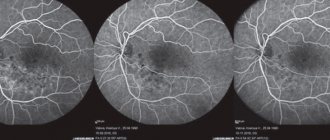

Ангиография сосудов глаза — что это такое? Ангиография — это один из методов рентгенографического